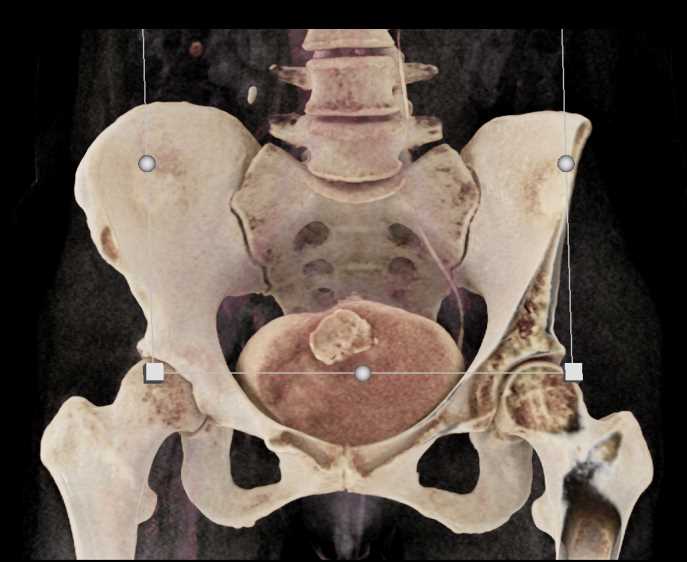

Urachal Carcinoma of the Bladder